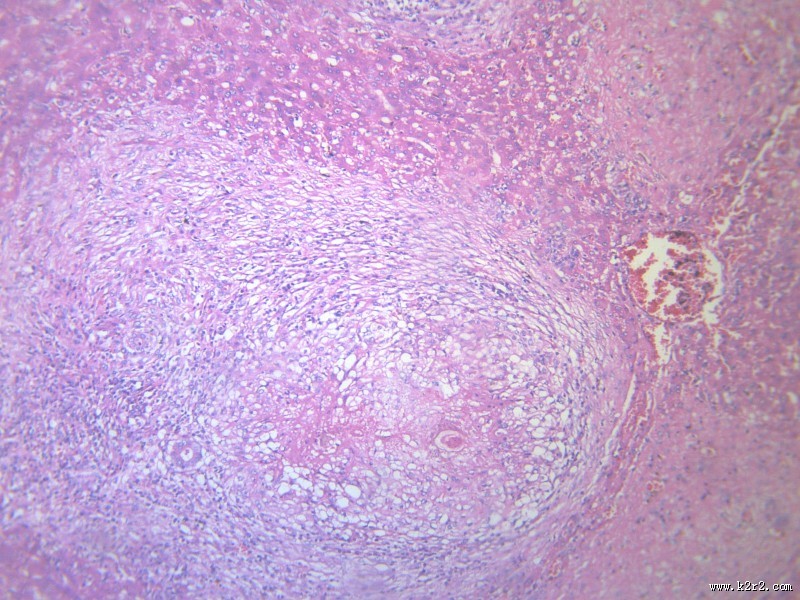

虫卵肉芽肿 - 第10张

一夕一夏上传虫卵肉芽肿 图集中 / 共有 12 张图片